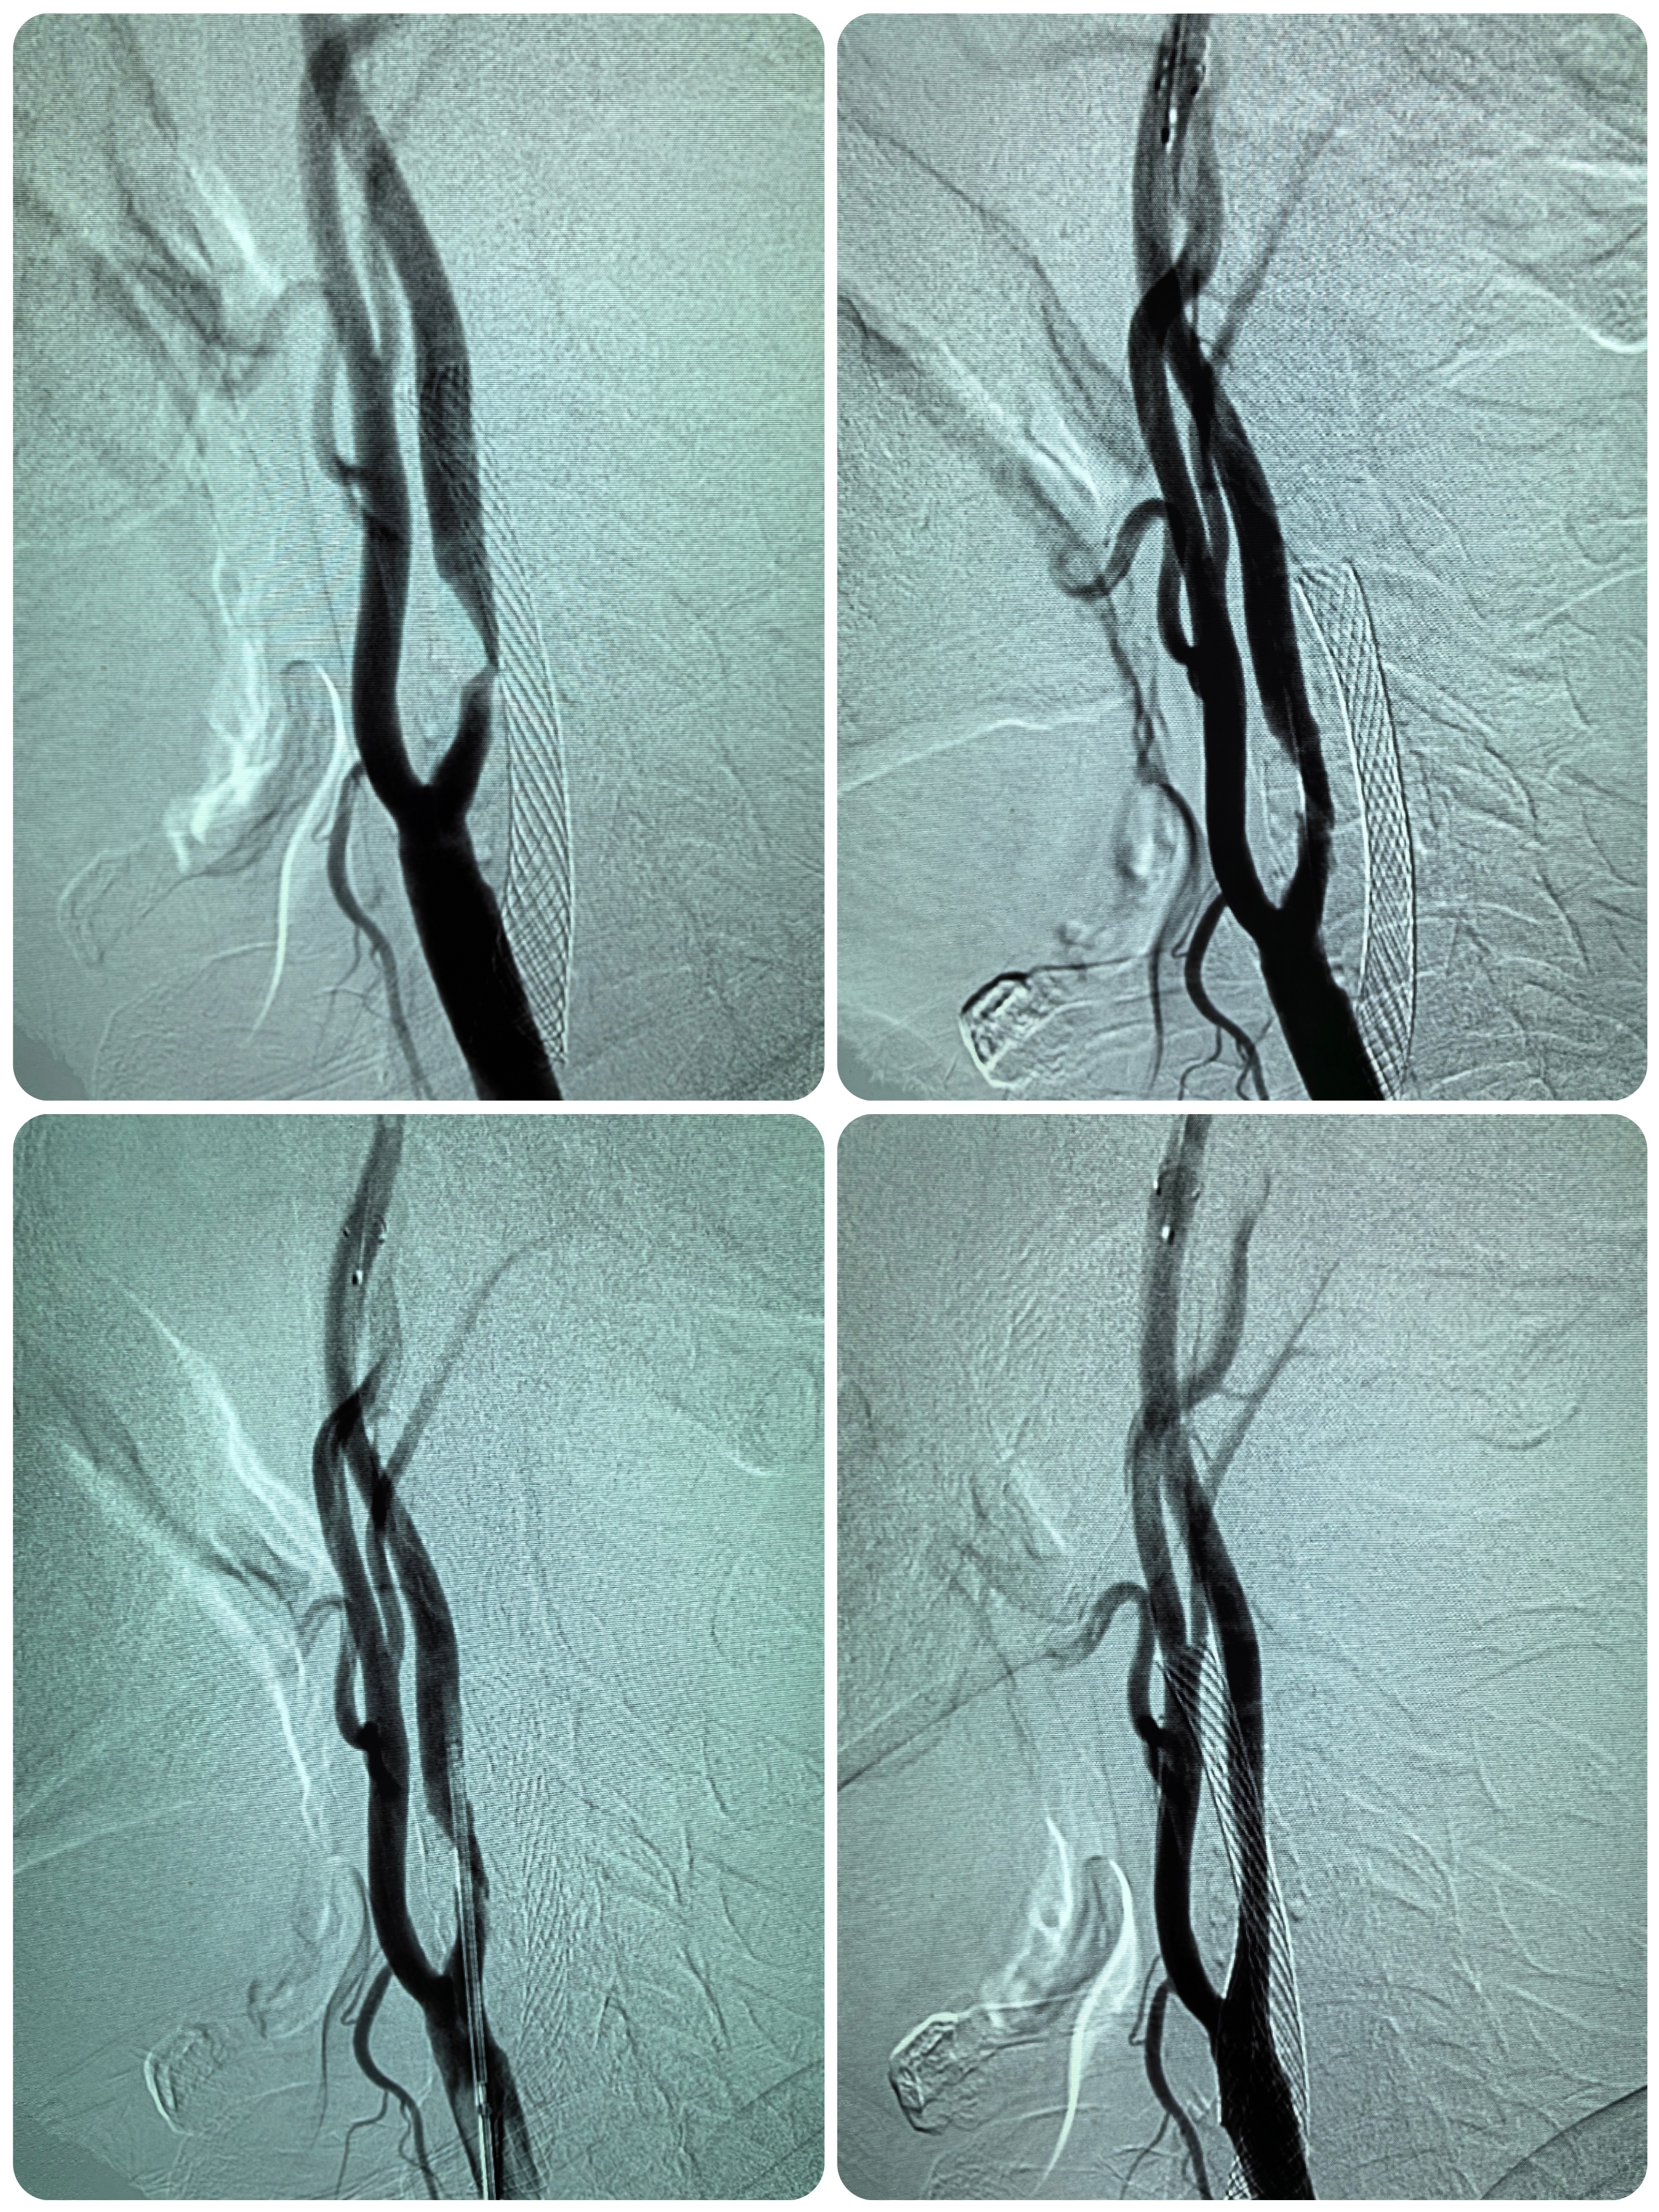

患者男性,70岁,体检发现双侧颈内动脉重度狭窄,1月前行右侧颈内动脉支架成形术,现为治疗左侧颈内动脉狭窄入院。既往高血压病史30年,口服硝苯地平控释片降压,血压控制130/80mmHg。

1、本例患者老年男性,双侧颈内动脉重度狭窄,治疗采取分期处理,间隔4周。

2、左侧颈内动脉从CTA看狭窄合并软斑,具备介入治疗指征。